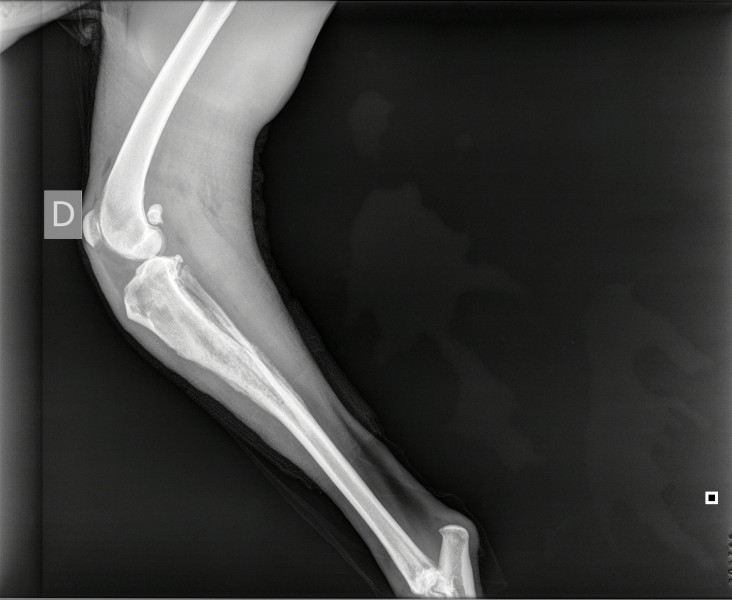

L’intervention sur le bassin de Mel a été une réussite, le chirurgien a atteint ses objectifs :

redresser le bassin, réaligner les abouts osseux fracturés puis stabiliser au moyen d’une

plaque avec vis qu’elle gardera à vie si elle le supporte bien.

Une radiographie de contrôle aura lieu dans 7-8 semaines ; durant ce temps, pas de course,

pas de saut et des sorties en laisse puis sera mis en place un programme de physiothérapie ;

Regardez sur les photos jointes, son bassin avant et après….

AVANT

APRES